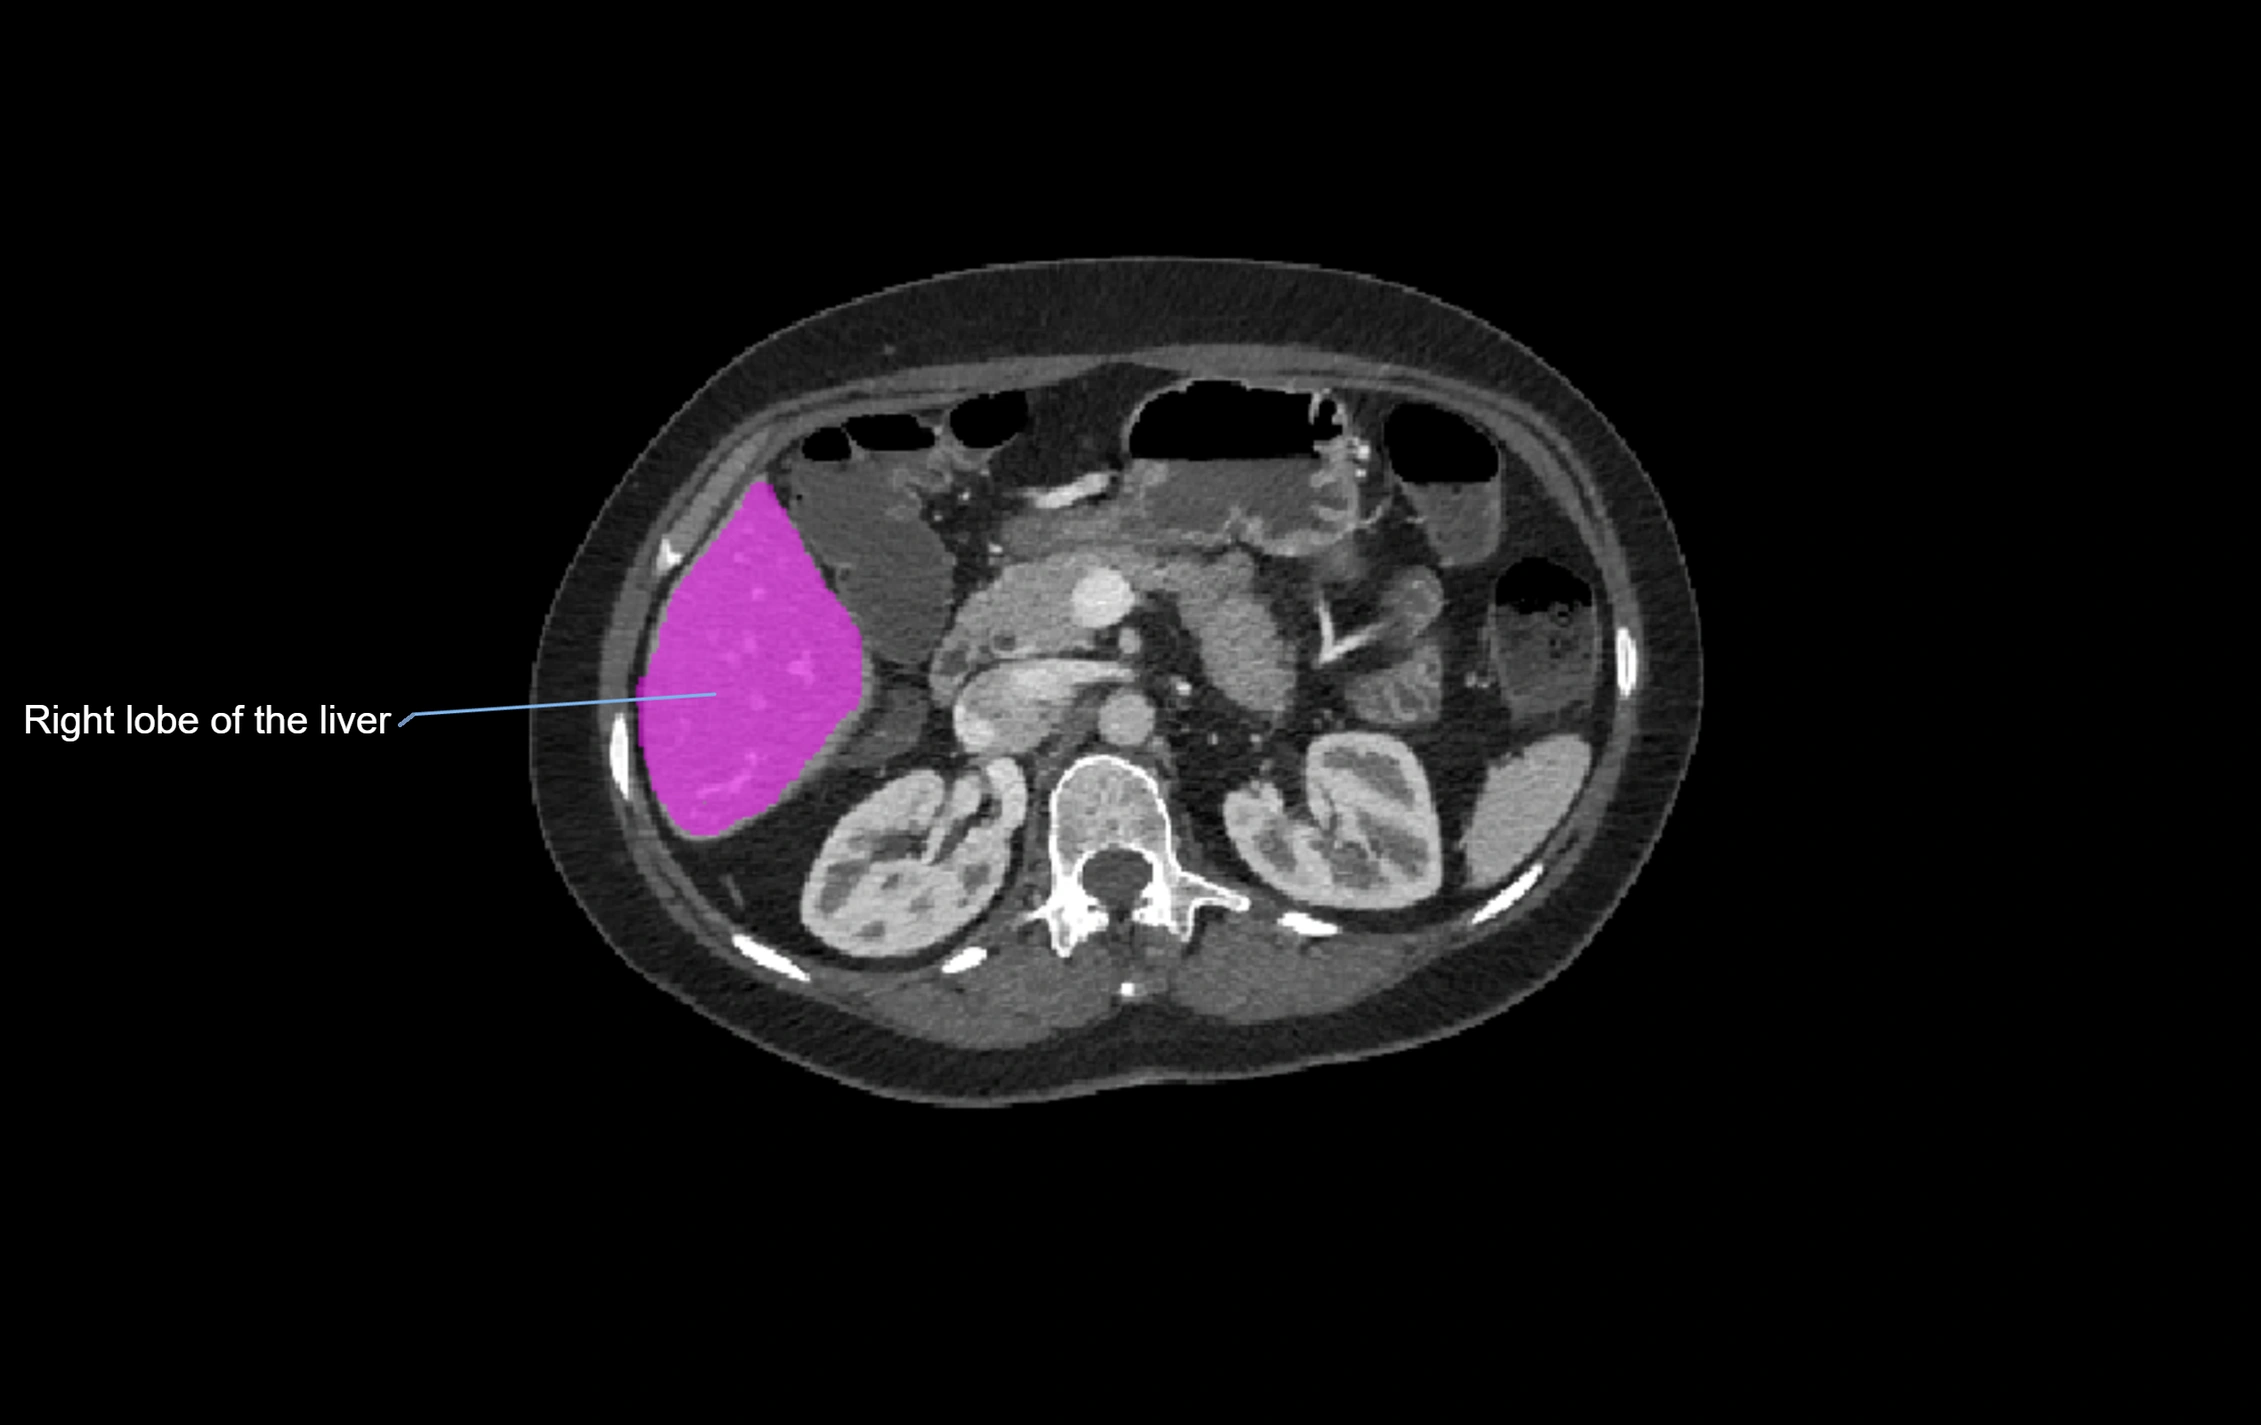

CT Image

image